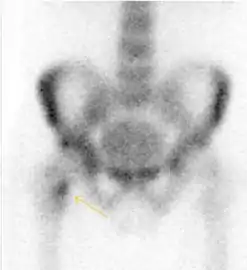

Nuclear Medicine

Bone scanning in people with hip pain can be complementary to other imaging studies, mainly in indeterminate bone lesions to clarify whether it is an active lesion with abnormal radiotracer accumulation. Nevertheless, MRI has replaced scintigraphy in the diagnosis of most of these conditions. An example is stress or insufficiency fractures: increased uptake is usually present in around 80% of fractures within 24 h, and 95% of fractures reveal activity by 72 h following trauma, showing an overall sensitivity of 93% and specificity of 95%. MRI is superior to bone scans in terms of sensitivity (99%-100%) and specificity (100%). Moreover, a bone scan does not provide detailed anatomical location of the fracture, and further imaging is usually required.[1]

Figure 10:

Stress femoral neck fracture in a young athlete barely visible in X-ray film as a sclerotic line (arrow)[1]

In this case, Tc 99 scintigraphy shows a band of uptake[1]